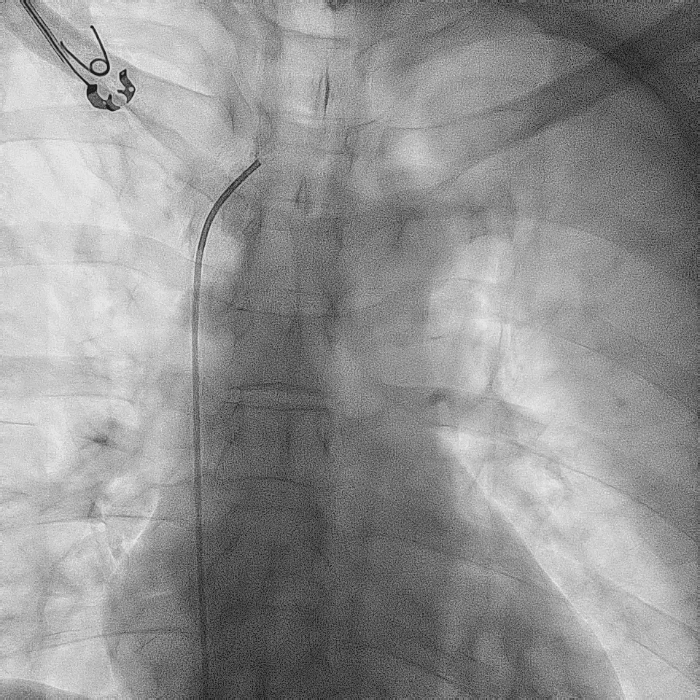

造影显示左侧无名静脉和上腔静脉交汇后

明显狭窄和闭塞

右心耳造影

拔除前进行猪尾造影,提前确认原右房导线位置为右心耳中部,心耳空间较大,解剖位置正常。为后续AVEIR™ AR植入做好计划,确认有足够空间避开原起搏导线所在位置。

RAO 30°造影

LAO 30°造影